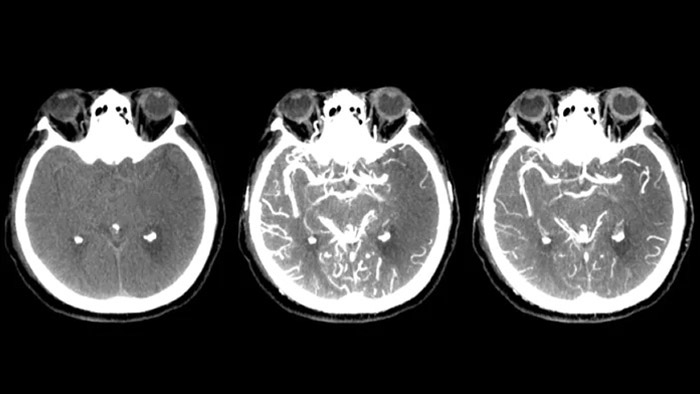

- Söderman M, Holmin S, Andersson T, Palmgren C, Babic D, Hoornaert B. Image noise reduction algorithm for digital subtraction angiography: clinical results. Radiology. 2013 Nov;269(2):553-60. Los resultados de la aplicación de las técnicas de reducción de dosis variarán en función de la tarea clínica, el tamaño del paciente, la ubicación anatómica y la práctica clínica. El radiólogo intervencionista, asistido por un físico si es necesario, debe determinar los ajustes adecuados para cada tarea clínica específica. Resultados basados en el producto dosis-área de la ASD por fotograma de un estudio prospectivo aleatorizado de un solo centro con 20 pacientes. Las series de ASD para Allura Xper con ClarityIQ y Allura Xper sin ClarityIQ se adquirieron en el canal frontal y lateral del mismo paciente bajo las mismas condiciones de geometría, campo de visión y protocolo de inyección. La calidad de la imagen se basó en una evaluación subjetiva (puntuación de 1 a 5, 1 = muy mala, 5 = excelente, con revisión a ciego por parte de 3 radiólogos que participaron en el estudio).